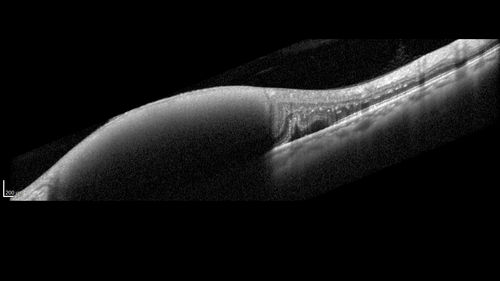

Macroaneurysm - Macular Hemorrhage - Branch Retinal Aterial Occlusion

62 year old African American female with chronic hypertension and vision loss for 2 weeks. VA is 20/400

Macroaneurym - Fresh Macular Hemorrhage - branch retinal arterial occulsion distal to MA